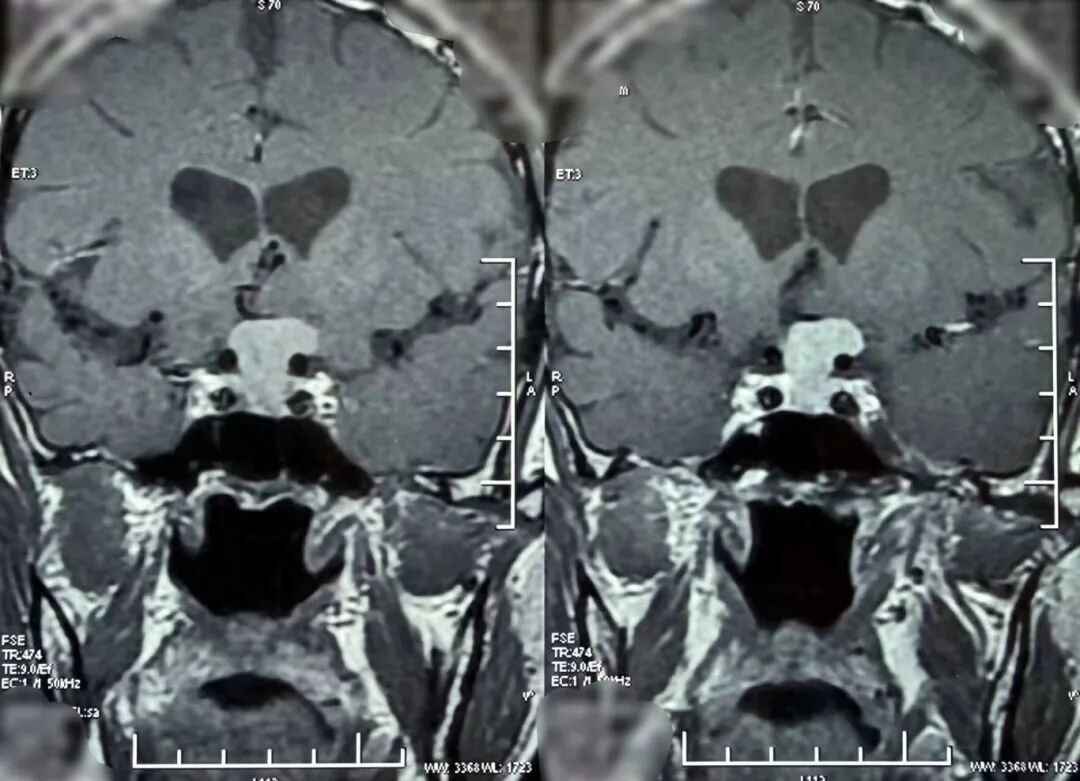

68岁的邓大叔是一位饱受垂体瘤困扰的“老战士”,11年前他经鼻行垂体瘤手术,几年后垂体瘤复发再次通过伽马刀治疗,经过两次历练后的他以为之后就可以高枕无忧,没想到近期的复查报告显示肿瘤“卷土重来”,且这次情况远比之前“棘手”,复发的肿瘤不仅从鞍内生长到鞍上,还与大脑的“生命线”——前交通动脉以及掌管意识记忆的三脑室底粘连紧密,甚至朝一侧颈内动脉上方生长,就像一颗埋在大脑深处的“不定时炸弹”,位置险要,结构复杂。

这颗复杂的“炸弹”究竟该如何拆除?张治国主任仔细研究了邓大叔的病情后,提出了一个大胆的方案:再次施行经鼻蝶微创手术。

最终,由张治国主任主刀,为邓大叔顺利实施了这例高难度的经鼻蝶微创手术,肿瘤被完整、精准地切除,紧密粘连的前交通动脉及三脑室底均保护完好。